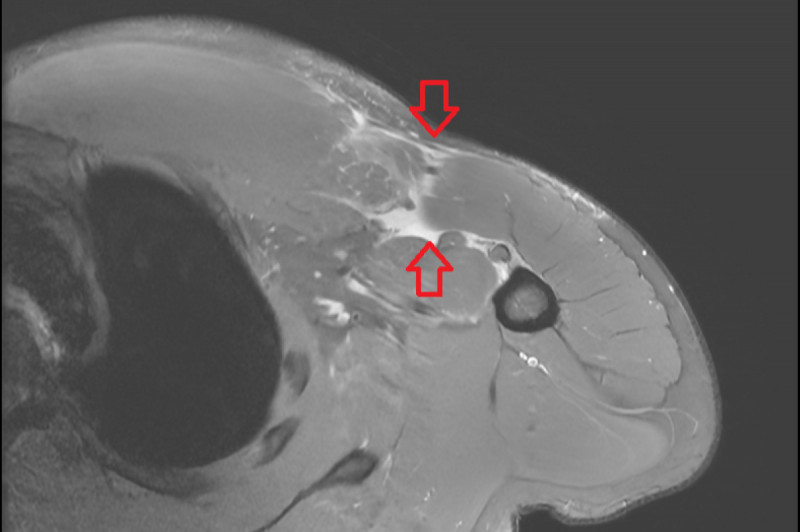

27歲林先生平常有規律健身習慣,某次進行臥推訓練,在休息時放下槓鈴的瞬間,突然感到右側胸口劇烈疼痛,右上肢越發無力,伴隨瘀青腫脹,赴醫院骨科求診,醫師藉由理學檢查與核磁共...…